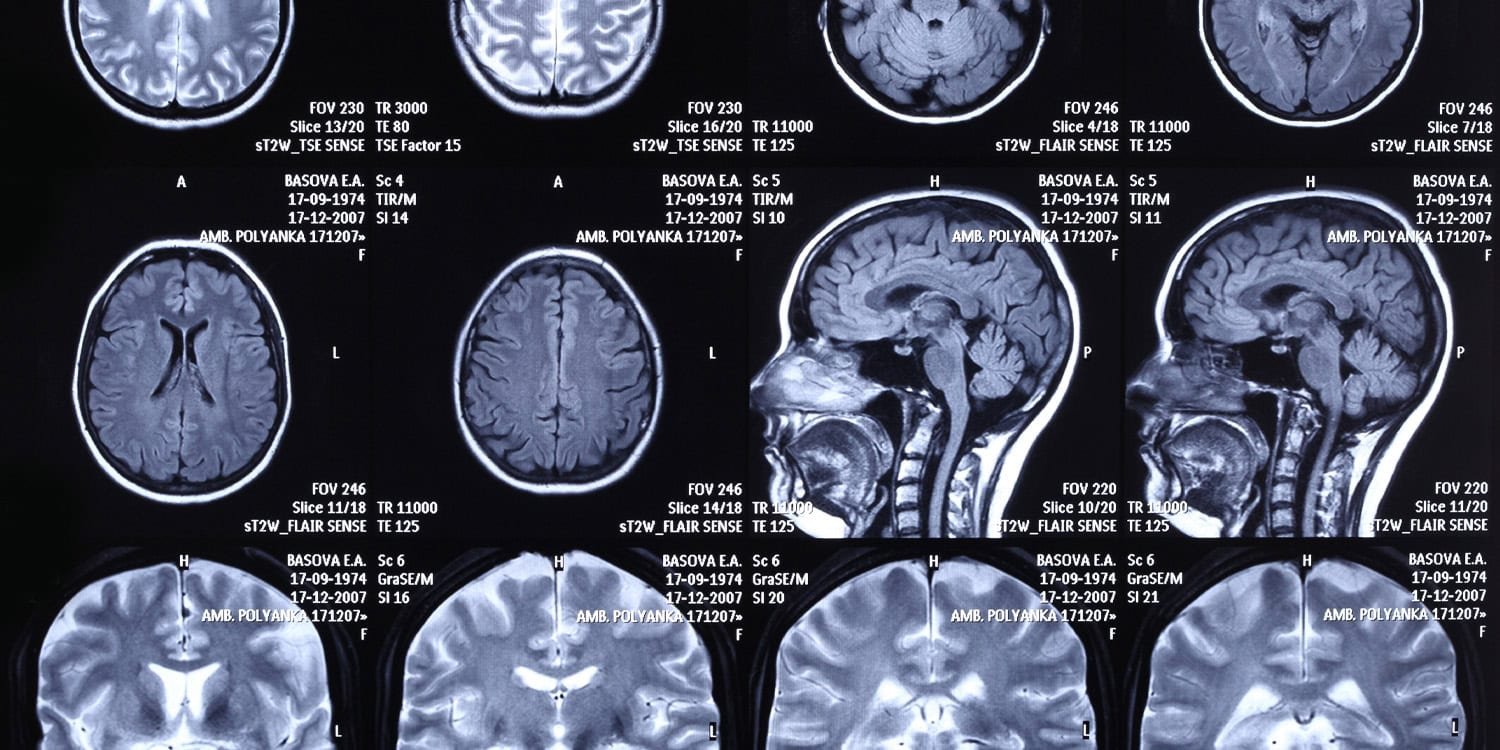

Participants were placed in a functional magnetic resonance imaging scanner. This machine uses a powerful magnetic field to track blood flow in the brain as it occurs. When certain areas of the brain work harder, they require more oxygen, and the scanner detects these subtle changes in blood oxygenation to map neural activity.

Brain scans showed a completely different picture. The thought processes driving these same food choices relied on different areas of the brain depending on the shopper’s political identity. The researchers conducted a whole-brain analysis to pinpoint where these differences occurred.

In Republican participants, brain scans showed increased activity in the left insula while choosing the mixed milk. The insula is an area often involved in interpreting internal sensations and assigning subjective value to items. Republicans also showed increased activity in the ventromedial prefrontal cortex, an area associated with introspection and evaluation of economic choices, when considering how to produce milk.

Among the Democratic participants, brain scans showed increased activity in the right precuneus and right superior frontal gyrus during combination egg choices. The precuneus is often associated with personal memory recall and the processing of social information. The superior frontal gyrus acts as a gateway for directing attention and managing cognitive resources.

The researchers took these brain activation patterns and fed them into a statistical model. They wanted to see if neural data alone could accurately classify participants as Republicans or Democrats. The model performed very well, correctly guessing a person’s political party between 76 and 94 percent of the time.

In one particular model, based entirely on brain activity when choosing egg combinations, the system correctly identified Democratic participants 100% of the time. These classification rates are very accurate compared to random guesses. It’s also better than traditional prediction methods that are simply based on how conservative a person’s parents happen to be.